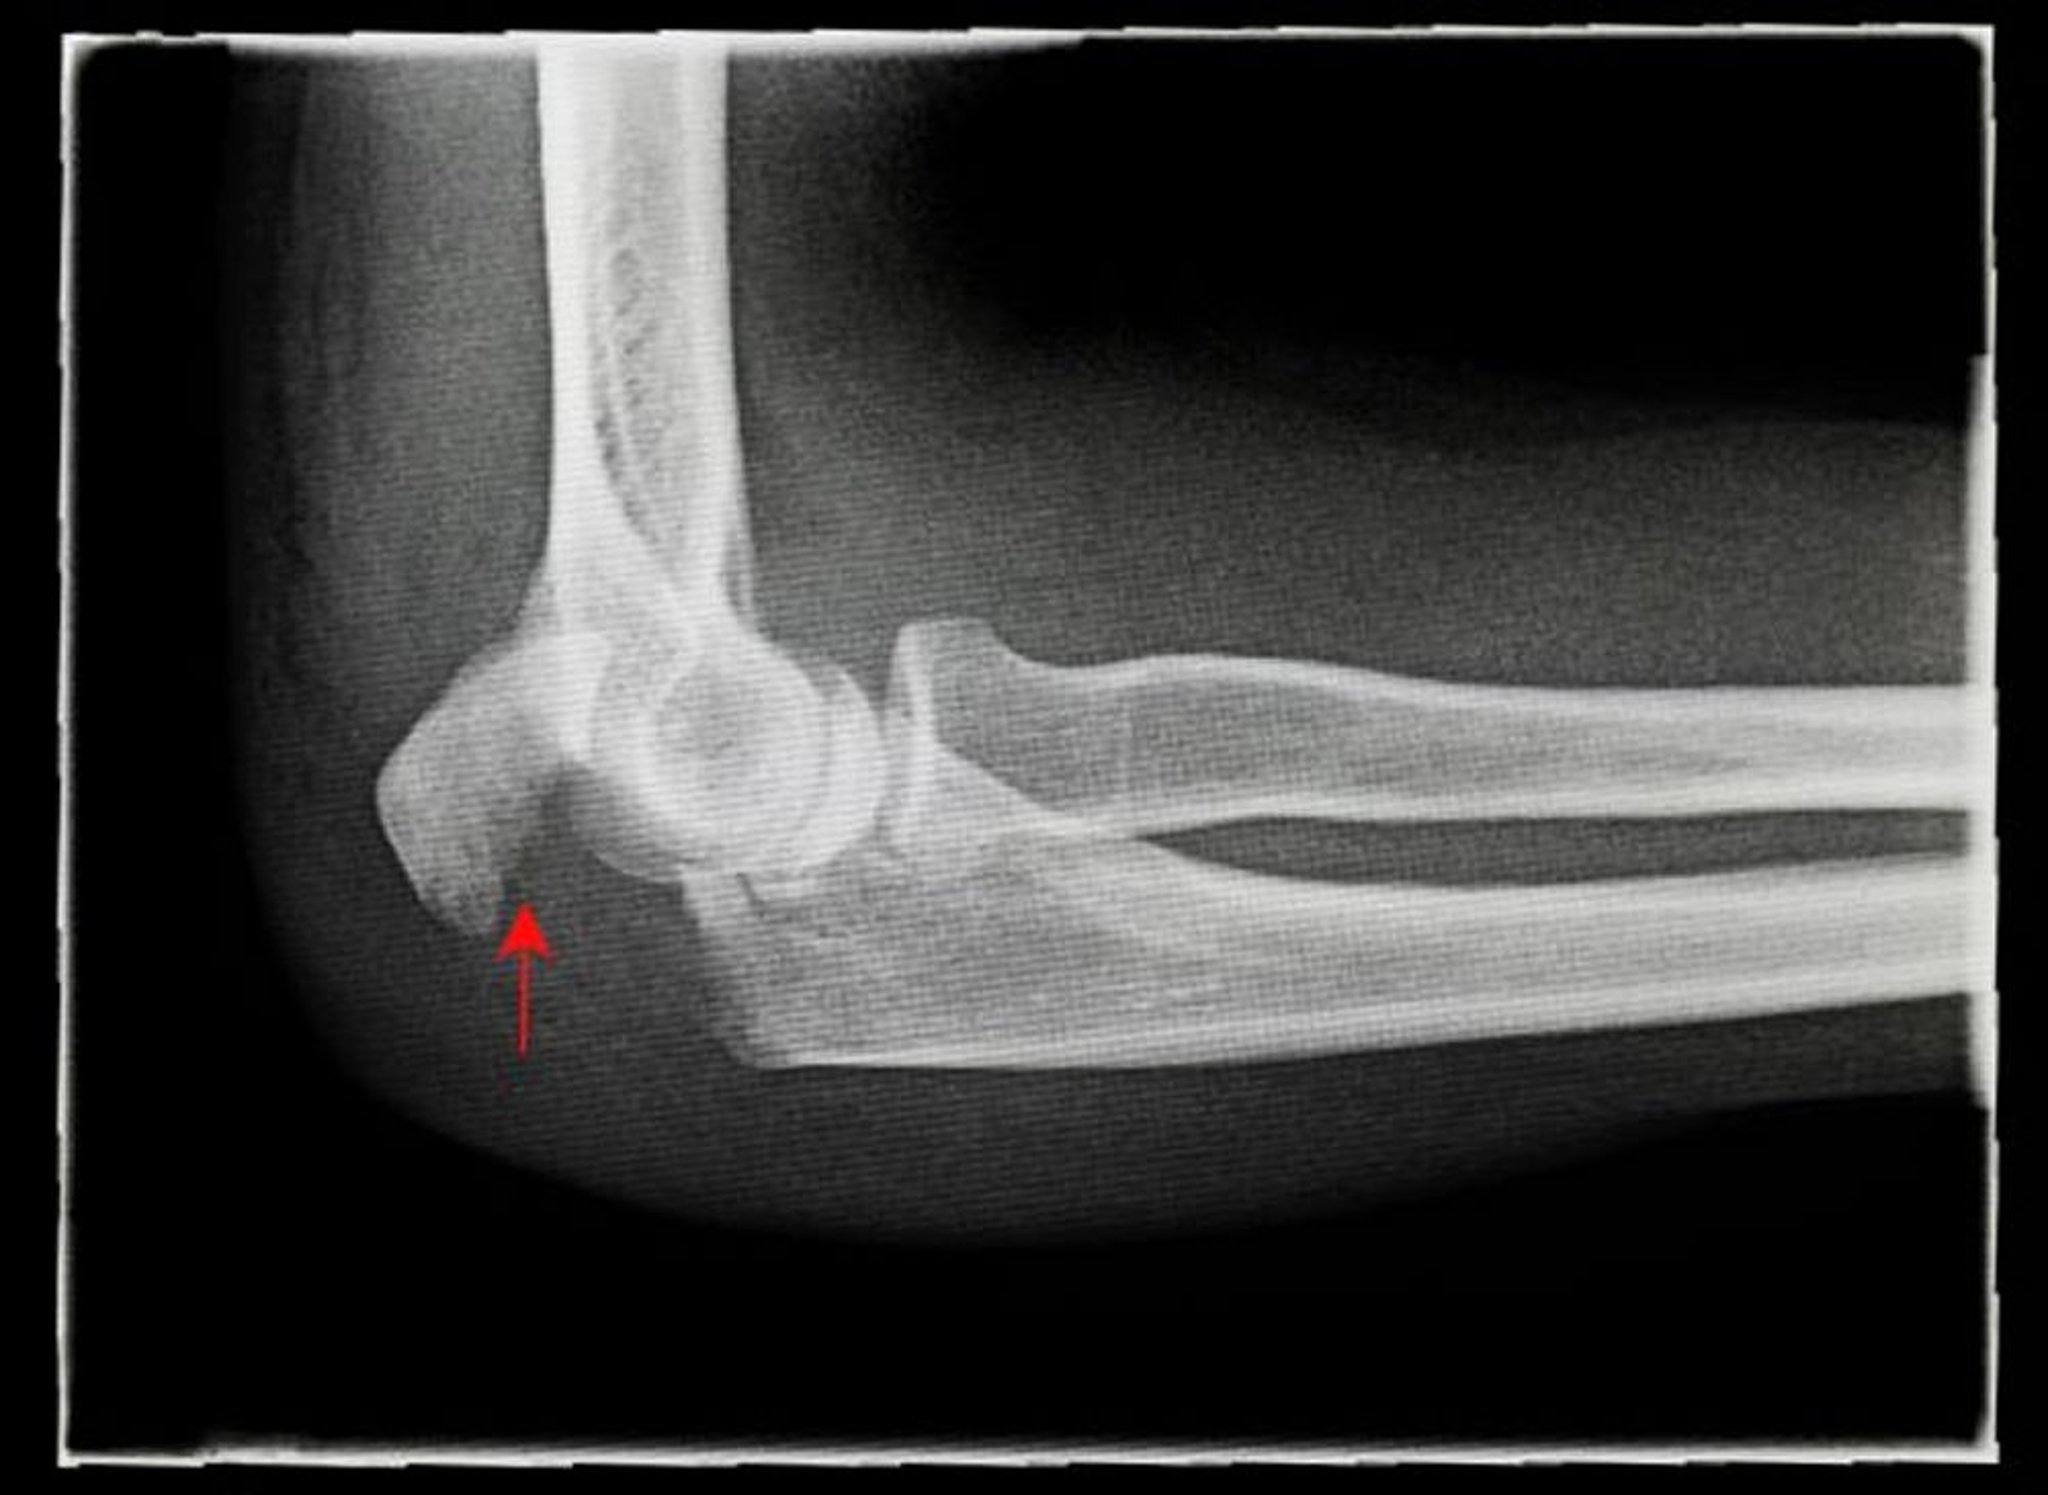

Fracture de l’olécrane avec déplacement

Cette radiographie montre une vue latérale d’une fracture de l’olécrane avec déplacement (flèche).